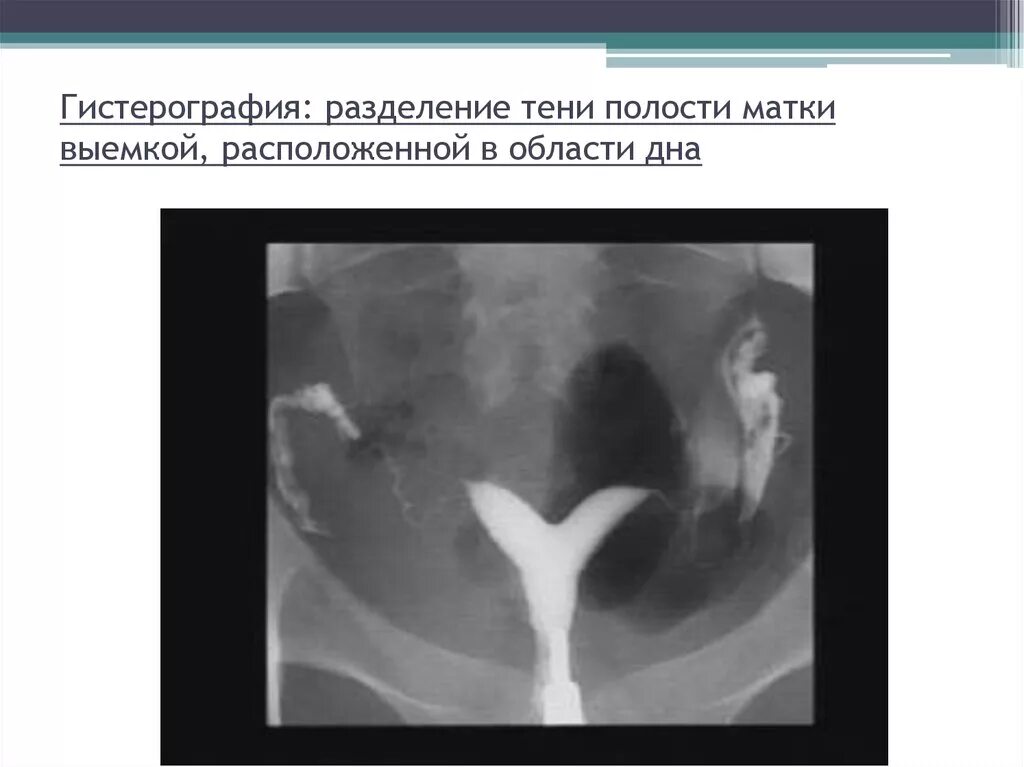

Аномалия полов орган